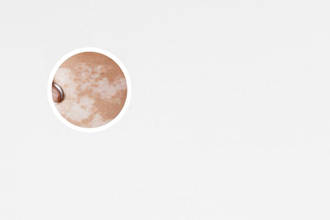

白癜風(fēng),給患者帶來(lái)了很多困擾。在治療白癜風(fēng)的過(guò)程中,311操作流程和注意事項(xiàng)是非常重要的。下面將從不同的維度來(lái)討論這些操作流程和注意事項(xiàng),幫助患者更好地應(yīng)對(duì)白癜風(fēng)。

白癜風(fēng),給患者帶來(lái)不少困擾。為了幫助患者更好地應(yīng)對(duì)白癜風(fēng),下面將介紹311操作流程和注意事項(xiàng)。

311操作流程主要包括三個(gè)步驟:前處理、治療和后處理。前處理主要是準(zhǔn)備工作,包括清潔皮膚表面、保護(hù)周圍健康皮膚、確定治療區(qū)域等。治療階段使用的是UVA波長(zhǎng)為311nm的燈光照射,這種波長(zhǎng)的光線能夠滲透到皮膚的深層,達(dá)到治療結(jié)果。治療時(shí)間根據(jù)病情的輕重以及病人的耐受程度而定,通常每次治療時(shí)間在幾分鐘至十幾分鐘之間。治療結(jié)束后,還需要進(jìn)行后處理工作,包括清潔皮膚、觀察治療后的反應(yīng)等。